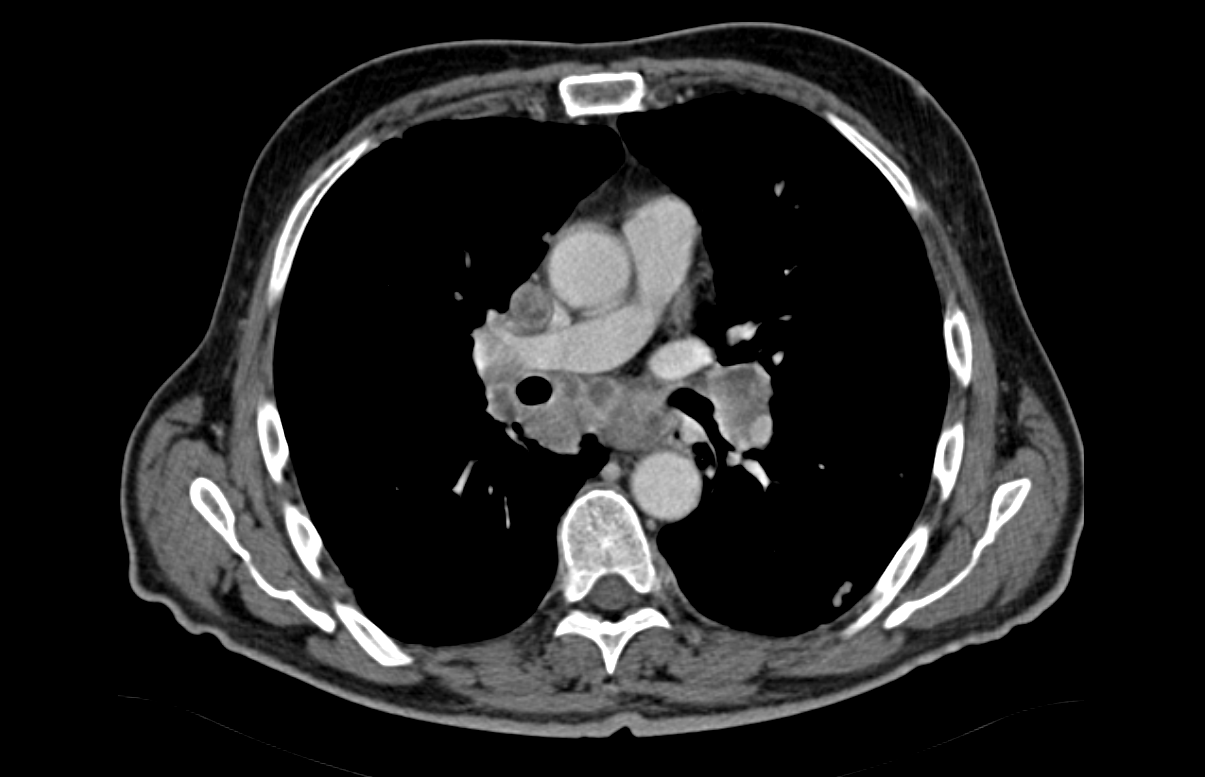

Αμφοτερόπλευροι πνευμονικοί όζοι ενδεικτικοί μεταστάσεων μελανώματος (Ευγενική παραχώρηση Dr. V. Penopoulos)